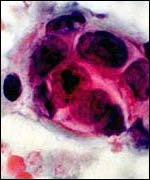

| Monday, 23 December, 2002, 11:58 GMT Cancer patient's check-up anger ![]() Women over 50 are all offered routine screening A south Wales woman who is in remission from breast cancer has told BBC Wales she was left in a state of uncertainty after her annual check-up was postponed twice. The 71-year-old, identified only as Joy, said she was told staff shortages at the clinic in the University Hospital of Wales in Cardiff were to blame.